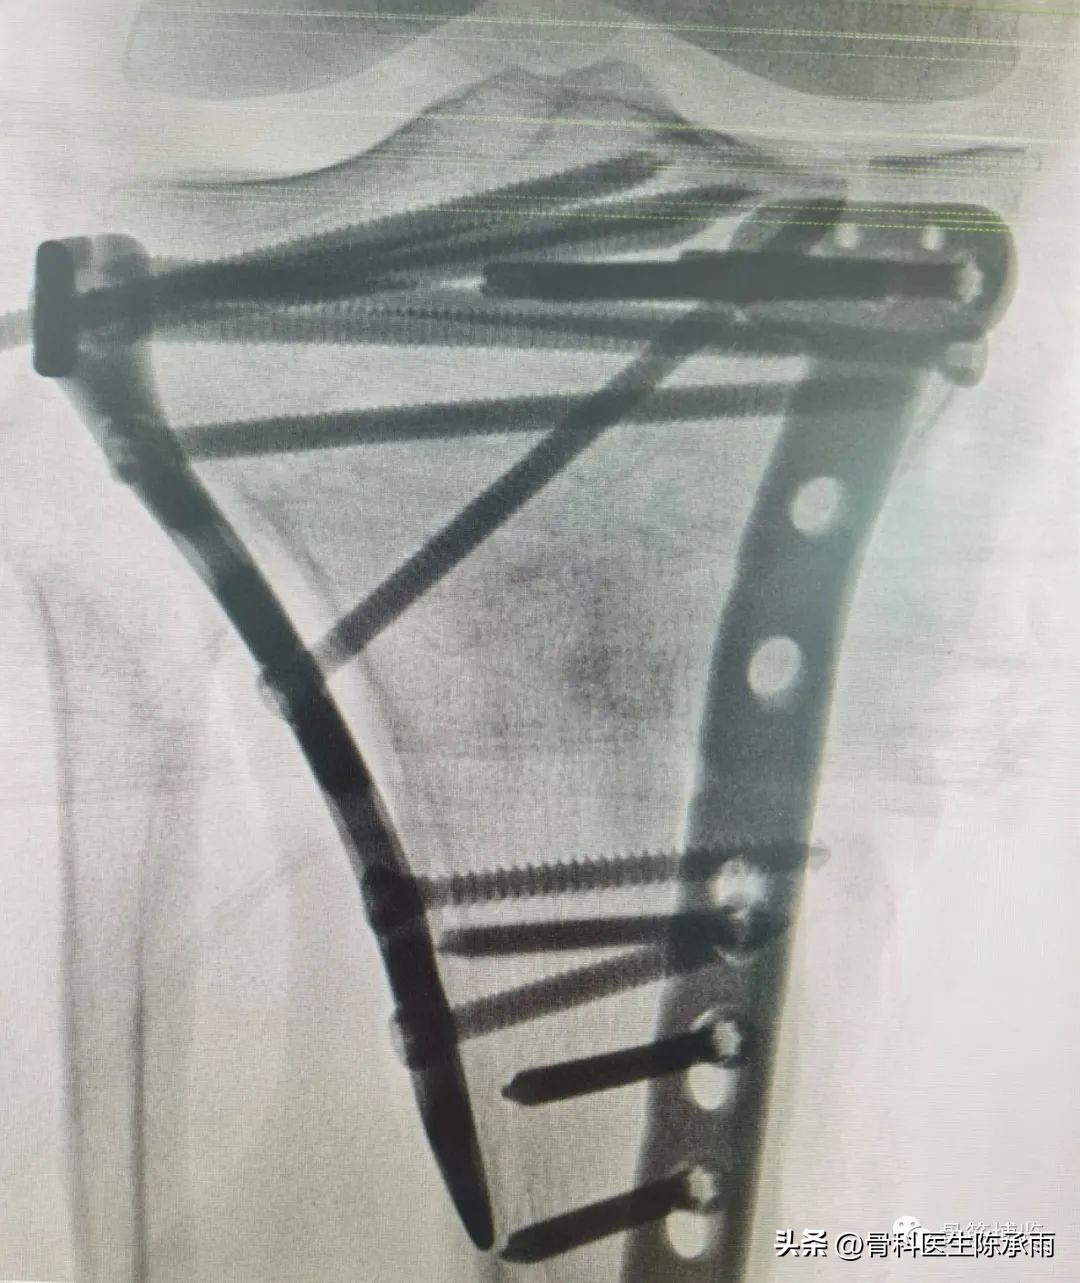

1例

2例

3例

4例

5例

6例

7例